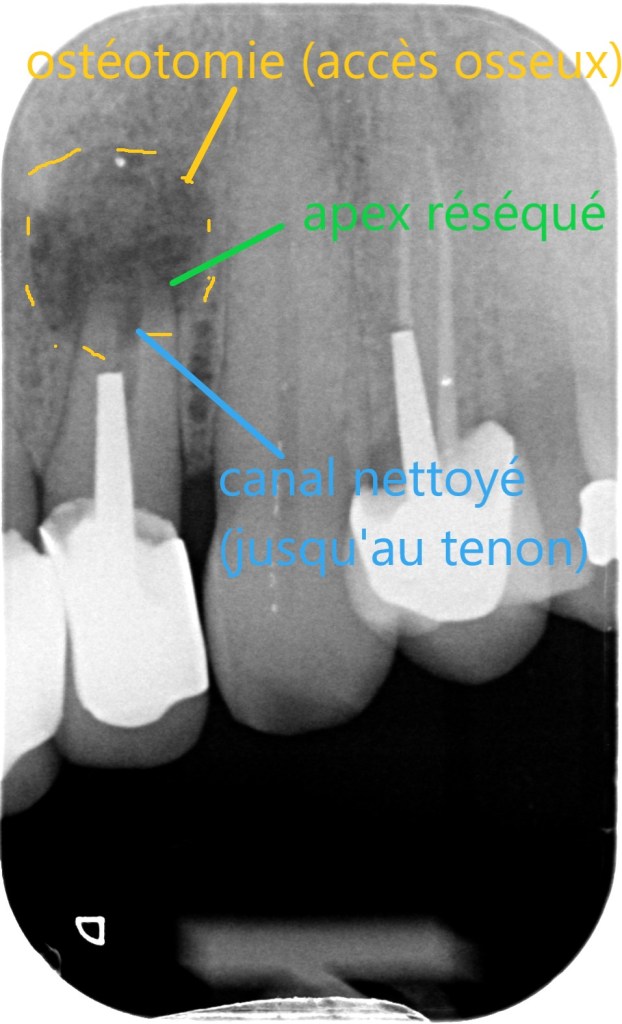

radio per-opératoire (apex réséqué et canal nettoyé a retro)

• L’apex de la dent est dégagé puis réséqué sur quelques millimètres. La lésion osseuse est curetée.

• Le canal de la dent est nettoyé sur quelques millimètres, désinfecté, puis obturé a retro.